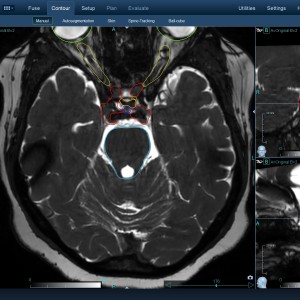

Στις παρακάτω φωτογραφίες θα δείτε παραδείγματα πλάνων θεραπείας καρκινικών όγκων με CyberKnife. Παρατηρήστε πόσο κοντά στους υγιείς ιστούς βρίσκονται οι καρκινικοί όγκοι που χρειάζεται να ακτινοβοληθούν. Μόνο με το CyberKnife και το προσωπικό πλάνο θεραπείας, μπορούν να ακτινοβοληθούν οι όγκοι χωρίς να πληγούν οι παρακείμενοι υγιείς ιστοί.

Με κόκκινο χρώμα περιγράφεται η περιοχή του όγκου.

Με μπλε, κίτρινο και πράσινο χρώμα περιγράφονται οι υγιείς ιστοί που δεν πρέπει να ακτινοβοληθούν.

Παρατηρήστε πόσο κοντά βρίσκεται ο όγκος με τους υγιείς ιστούς.